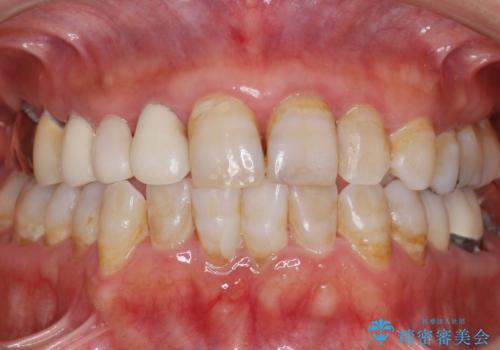

- 被せ物がかけてしまったことを主訴に来院された患者様です。

口腔内を精査したところ、右上のブリッジの内側(口蓋側)がかけており、下の前歯(右下1)には唇舌側に瘻孔を伴う大きな根尖病変ができていました。

右上のブリッジ(右上④3②)のやりかえと、下の前歯(右下1)の根管治療を行った後セラミッククラウンによる補綴治療を行いました。

とにかく早く終わらせたいとのご希望により、1回の治療時間を長くおとりして治療期間の短縮に努めました。

(初診を含め、治療期間:2ヶ月、来院回数:7回)